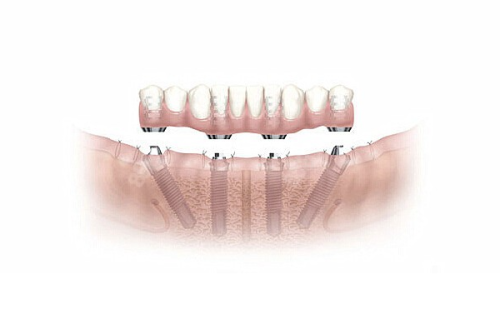

| 半口All - on - 4种植 | 38000 | 36100(9.5折) |